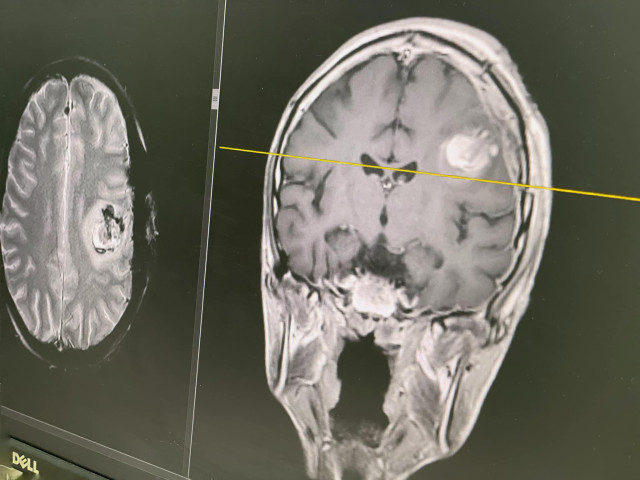

Ті після ретельного обстеження дійшли висновку, що єдиний шанс для Максима – це операція на мозку з пробудженням – AWAKE SURGERY.«Далі тягнути нема куди. Наріс набряк навколо. Є вже ознаки того, що ця пухлина добряче тисне на мозок. Це ризик смерті. Тому однозначно потрібно це лікувати. Обов’язково потрібно видаляти», – сказав завідувач нейрохірургічного відділення Михайло Ловга.Під час найважливішої частини операції – видалення самої пухлини – лікарям вдалося розбудити Максима. Це потрібно, аби контролювати його мову та рухи і не пошкодити ділянки мозку, що за них відповідають.Медики розважали Максима розмовами про його улюблених супергероїв коміксів та вигадані всесвіти і не давали хлопцеві заснути. Поки він говорив, активність у ділянках, які відповідають за рухи кінцівками та мовлення, фіксували нейрофізіологи Марія Павлюк та Юлія Галій-Герасимович.Операція тривала сім годин. Після неї Максим на радість мамі та медикам заговорив ще краще, ніж до втручання. Результати МРТ теж обнадійливі: лікарям вдалося повністю видалити пухлину. А гістологічне дослідження показало, що утворення було доброякісним. І подальшого лікування пацієнт не потребує. Епілептичних нападів більше немає.За тиждень після операції з пробудженням Максима виписують.